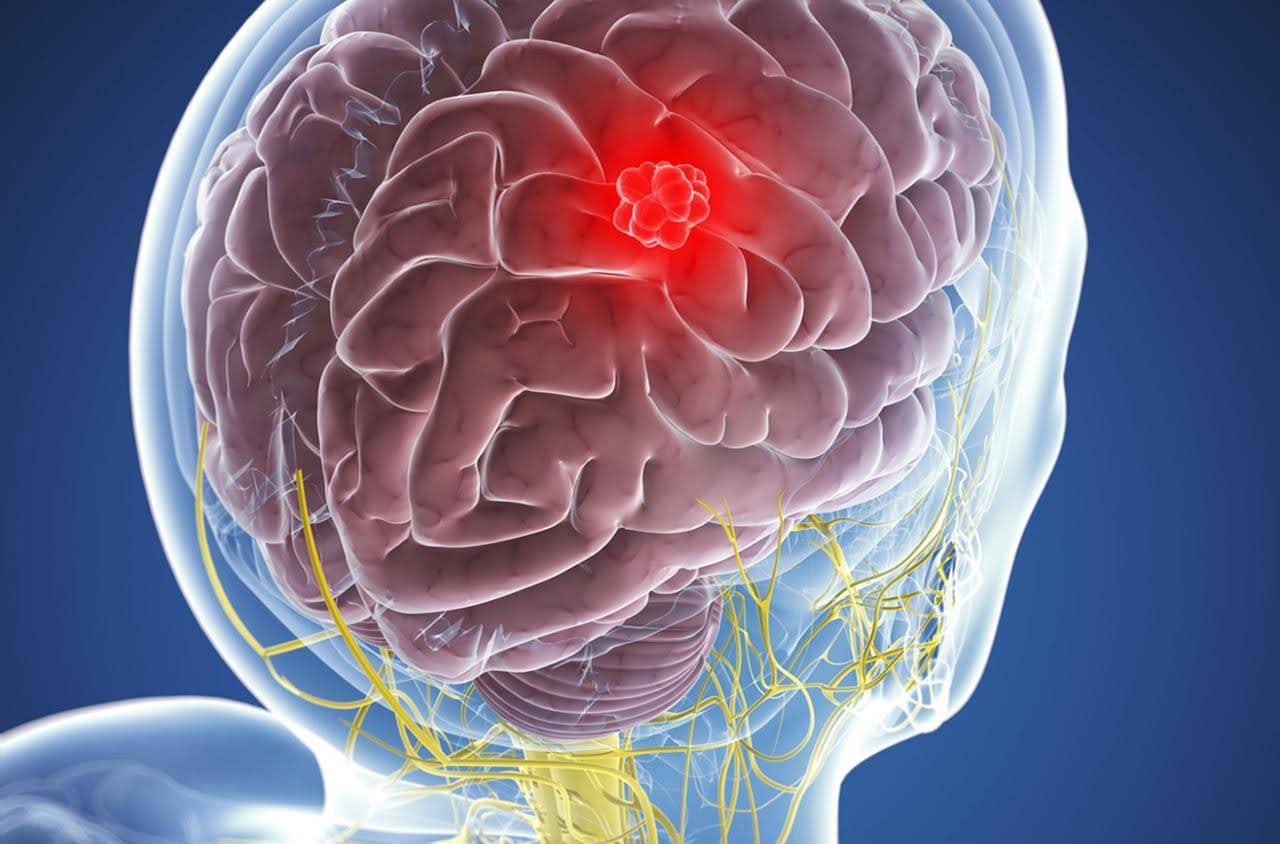

Meningioma: Una Guía para Pacientes

## ¿Qué es un meningioma?El meningioma es un tipo de tumor que se origina en las meninges, las me...